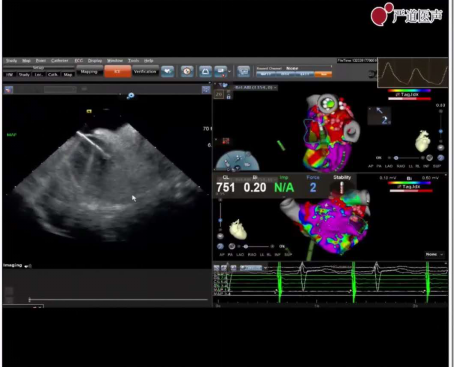

手术由肖方毅教授完成,本例患者采用温附一特色UPS+Flavor一站式术式治疗。采用温附一特色双穿刺房间隔的方式:首先在三维超声下标记两次房间隔穿刺位点,第1针在三维腔内超声指导下进行卵圆窝较低位房间隔进行穿刺,建议保留钢丝后撤鞘;而后进行第2次穿刺,在三维腔内超声指导下在较高位进行二次穿刺,达到最少干扰最优穿刺位点的效果。穿刺完成后顺利在AI指导下完成肺静脉消融,同时全程监测心包安全。消融后进行温附一特色Flavor左心耳封堵术,超声下回撤消融导管和标测导管,并将三维心腔内超声送入左心房。通过0度、45度、90度、135度4个长轴角度评估左心耳的大小。通过三维心腔内超声和X涉嫌下造影进行判断选择合适的封堵器,在超声指导下通过鞘管植入封堵器,应用温附一MARK术式打开封堵器,并通过4个长轴角度评估封堵器于左心耳的关系。最后,造影结合牵拉左心耳封堵器,判断位置关系和分流情况良好,释放封堵器。UPS结合Flavor术式顺利完成一站式手术,顺利下台。